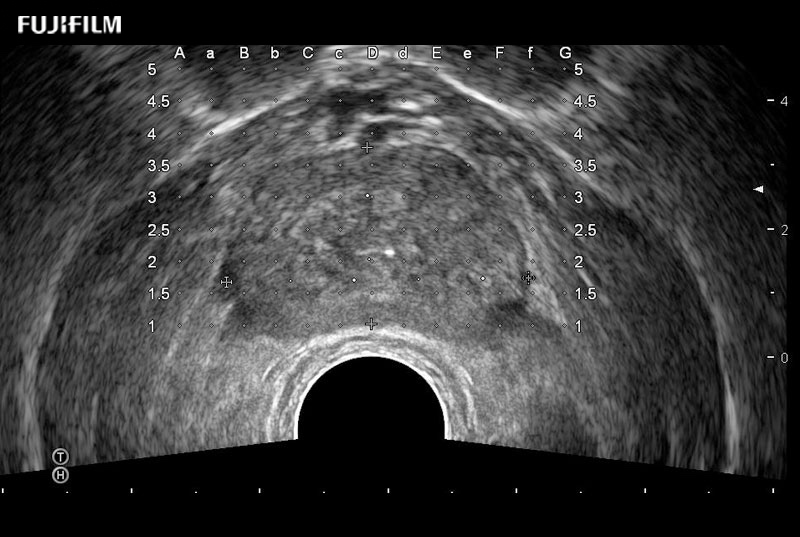

Exclusive 200° FOV end-fire prostate biopsy transducer.

Main Specifications:

Provides real-time imaging of both the sagittal and transverse planes